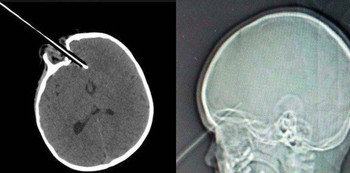

Saat itulah ia tersandung di tangga sambil memegang pensil. Seperti yang terlihat pada hasil foto sinar X, pensil tajam tersebut menikam matanya dan kemudian menembus sepanjang hampir 4 cm di bagian depan otaknya.